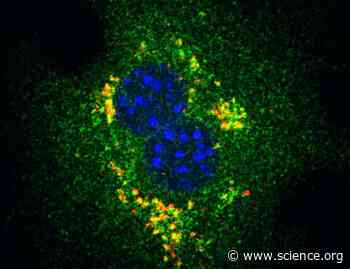

The E3 ligase TRIM13 restrains LPS-induced inflammation by reducing STIM1 abundance and the IRE1α-dependent unfolded protein response | Science Signaling

Glycerol 3-phosphate activates lipid metabolism through GATOR2-dependent regulation of mTORC1 | Science Signaling

A molecular glue to take down mutant BRAF | Science Signaling